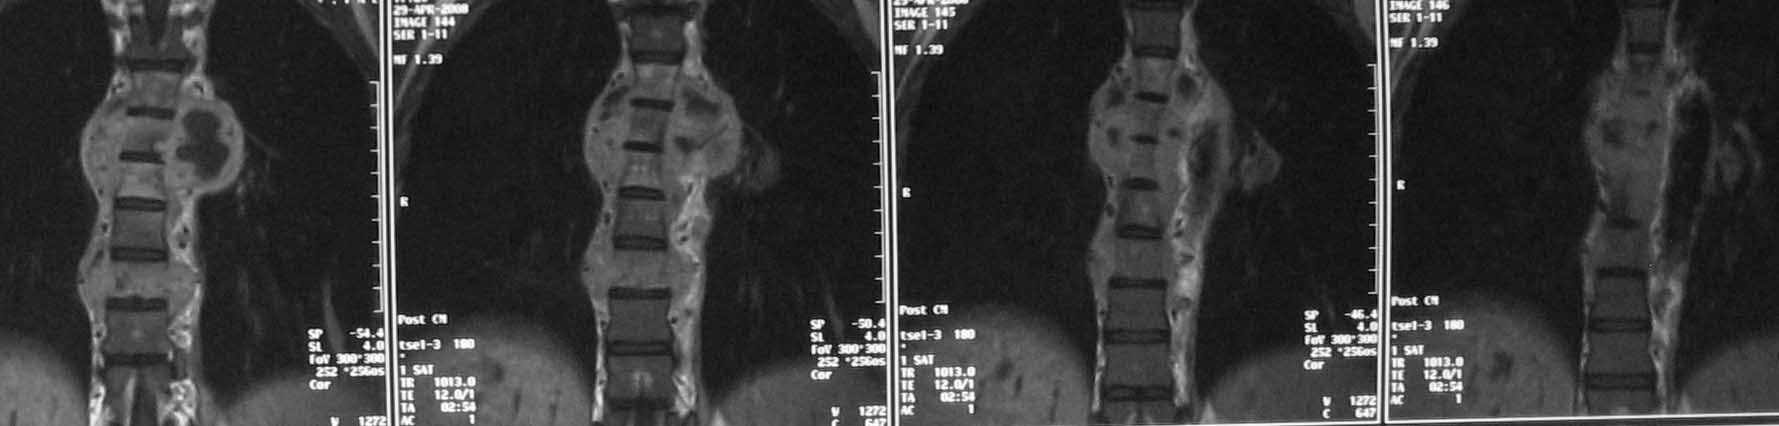

Доплнительное изображение 3. спинной мозг максимально компримирован на уровне 6 грудного позвонка.

Отправьте ЯМР сканы в сагитальной плоскости (скан во фронтальной плоскости может дать ложное представление об уровне компрессии спинного мозга за счет грудного кифоза).

В решении вопроса о протяженности резекции тел позвонков, считаю нецелесообразным ориентироваться на данные МРТ, в том числе на МР реконструкции, так как значительное повышение Т2 сигнала, которое мы видим на представленных снимках, появляется уже на первой неделе заболевания вследствие цитотоксического отёка и только потом некроза (С.А. Тиходеев, А.А. Вишневский «Неспецифический остеомиелит позвоночника» 2004). На представленных КТ тело позвонка (м.б. ThVI?) повреждено полностью и задние его отделы включительно, по всей видимости, этот уровень соответствует максимальной компрессии спинного мозга.